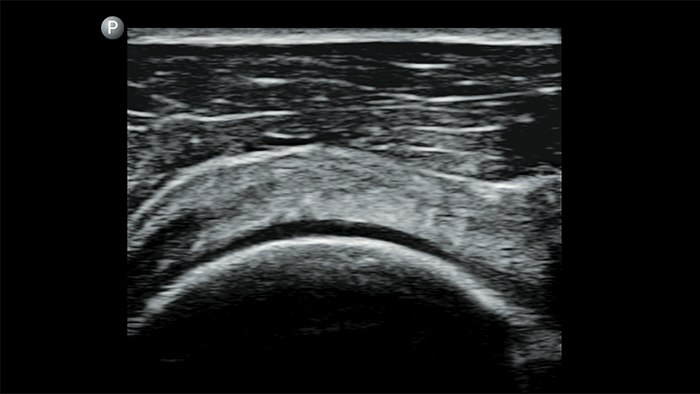

Breathe easier with Lumify

Lumify can help assess patients faster and improve accuracy when diagnosing common causes of dyspnea and other lung conditions.